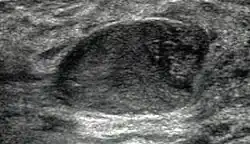

Mammographisch erscheinen Fibroadenome meist als umschriebene Raumforderungen, die je nach Alter der Läsion sichtbare grobschollige Verkalkungen aufweisen können. Bei Ultraschalluntersuchungen zeigt sich die Läsion ebenfalls umschrieben, homogen und hypoechogen sowie mit posteriorer Schallverstärkung. Unter Umständen können der gelappte Aufbau und eine dünne kapsuläre Begrenzung sichtbar sein. Die Magnetresonanztomographie demonstriert einen glatt begrenzten Herdbefund mit hoher Signalintensität bei T2-Wichtung und Einsatz Gadolinium-haltiger Kontrastmittel.